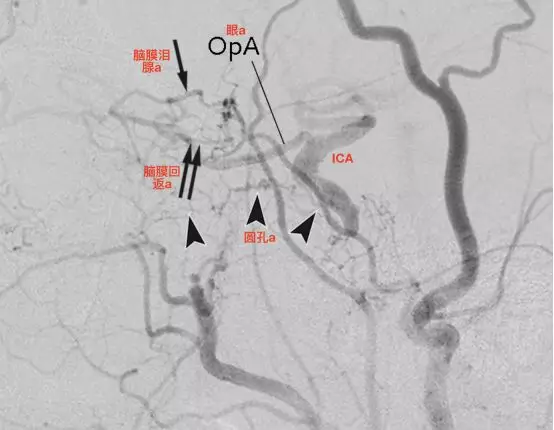

颈内动脉闭塞,来自上颌内动脉分支的代偿。a,颈总动脉造影侧位,眼动脉由脑膜泪腺动脉(单箭)和脑膜回返动脉(双箭)代偿。通过圆孔动脉(箭头)代偿血流至下外侧干(Tanoue 2013)。

b,颈总动脉造影,动脉早期,侧位,颈内动脉发自翼管动脉(箭头)(Tanoue 2013)。

c,颈总动脉造影,动脉晚期,侧位,显示远端颈内动脉(Tanoue 2013)。